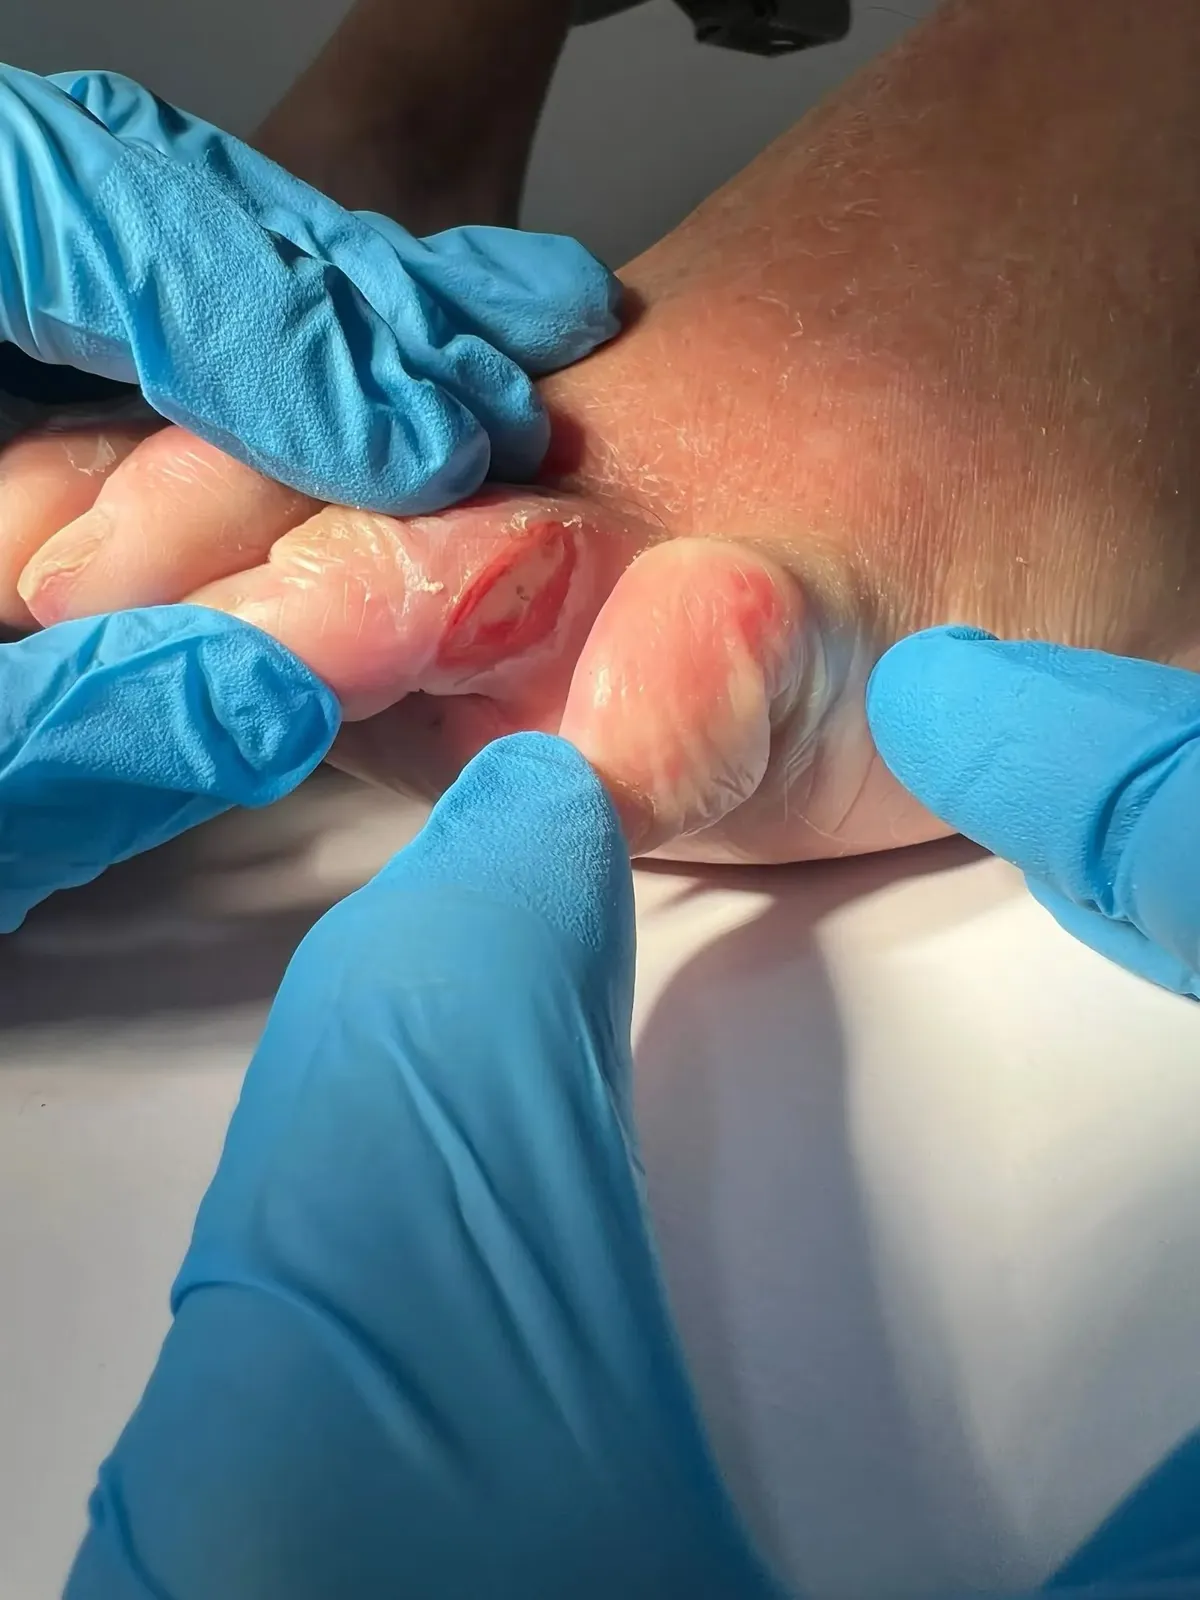

Exploración clínica detallada de pigmentación ungueal en consulta

2. Exploración Ungueal: Inspección visual comparativa, palpación (dolor, movilidad), búsqueda signo de Hutchinson.

Lo que encontramos: Durante la exploración observamos una banda marrón homogénea, bordes regulares, sin invasión de piel periungueal (signo de Hutchinson negativo). Realizamos dermatoscopia digital que mostró patrón de pigmentación regular. La ecografía ungueal confirmó grosor normal del lecho ungueal sin masas subyacentes.

3. Dermatoscopia: Visualización ampliada (10-70x), patrones pigmentarios, diferenciación benigna/sospechosa.